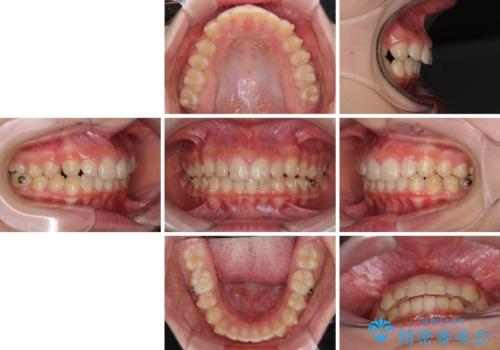

- ヨーロッパにてインビザライン矯正を始めたものの、日本に転居することになり、治療の継続を希望して来院された患者様です。

治療計画に無理がなく、現地担当医と速やかに連絡が取れるとのことで、インビザライン社での転医手続きを行い、継続して治療を行うこととしました。

舌の突出癖により、上下前歯が非接触となっていたため、トレーニングを徹底的に指導し、安定した咬み合わせにより終了させることができました。